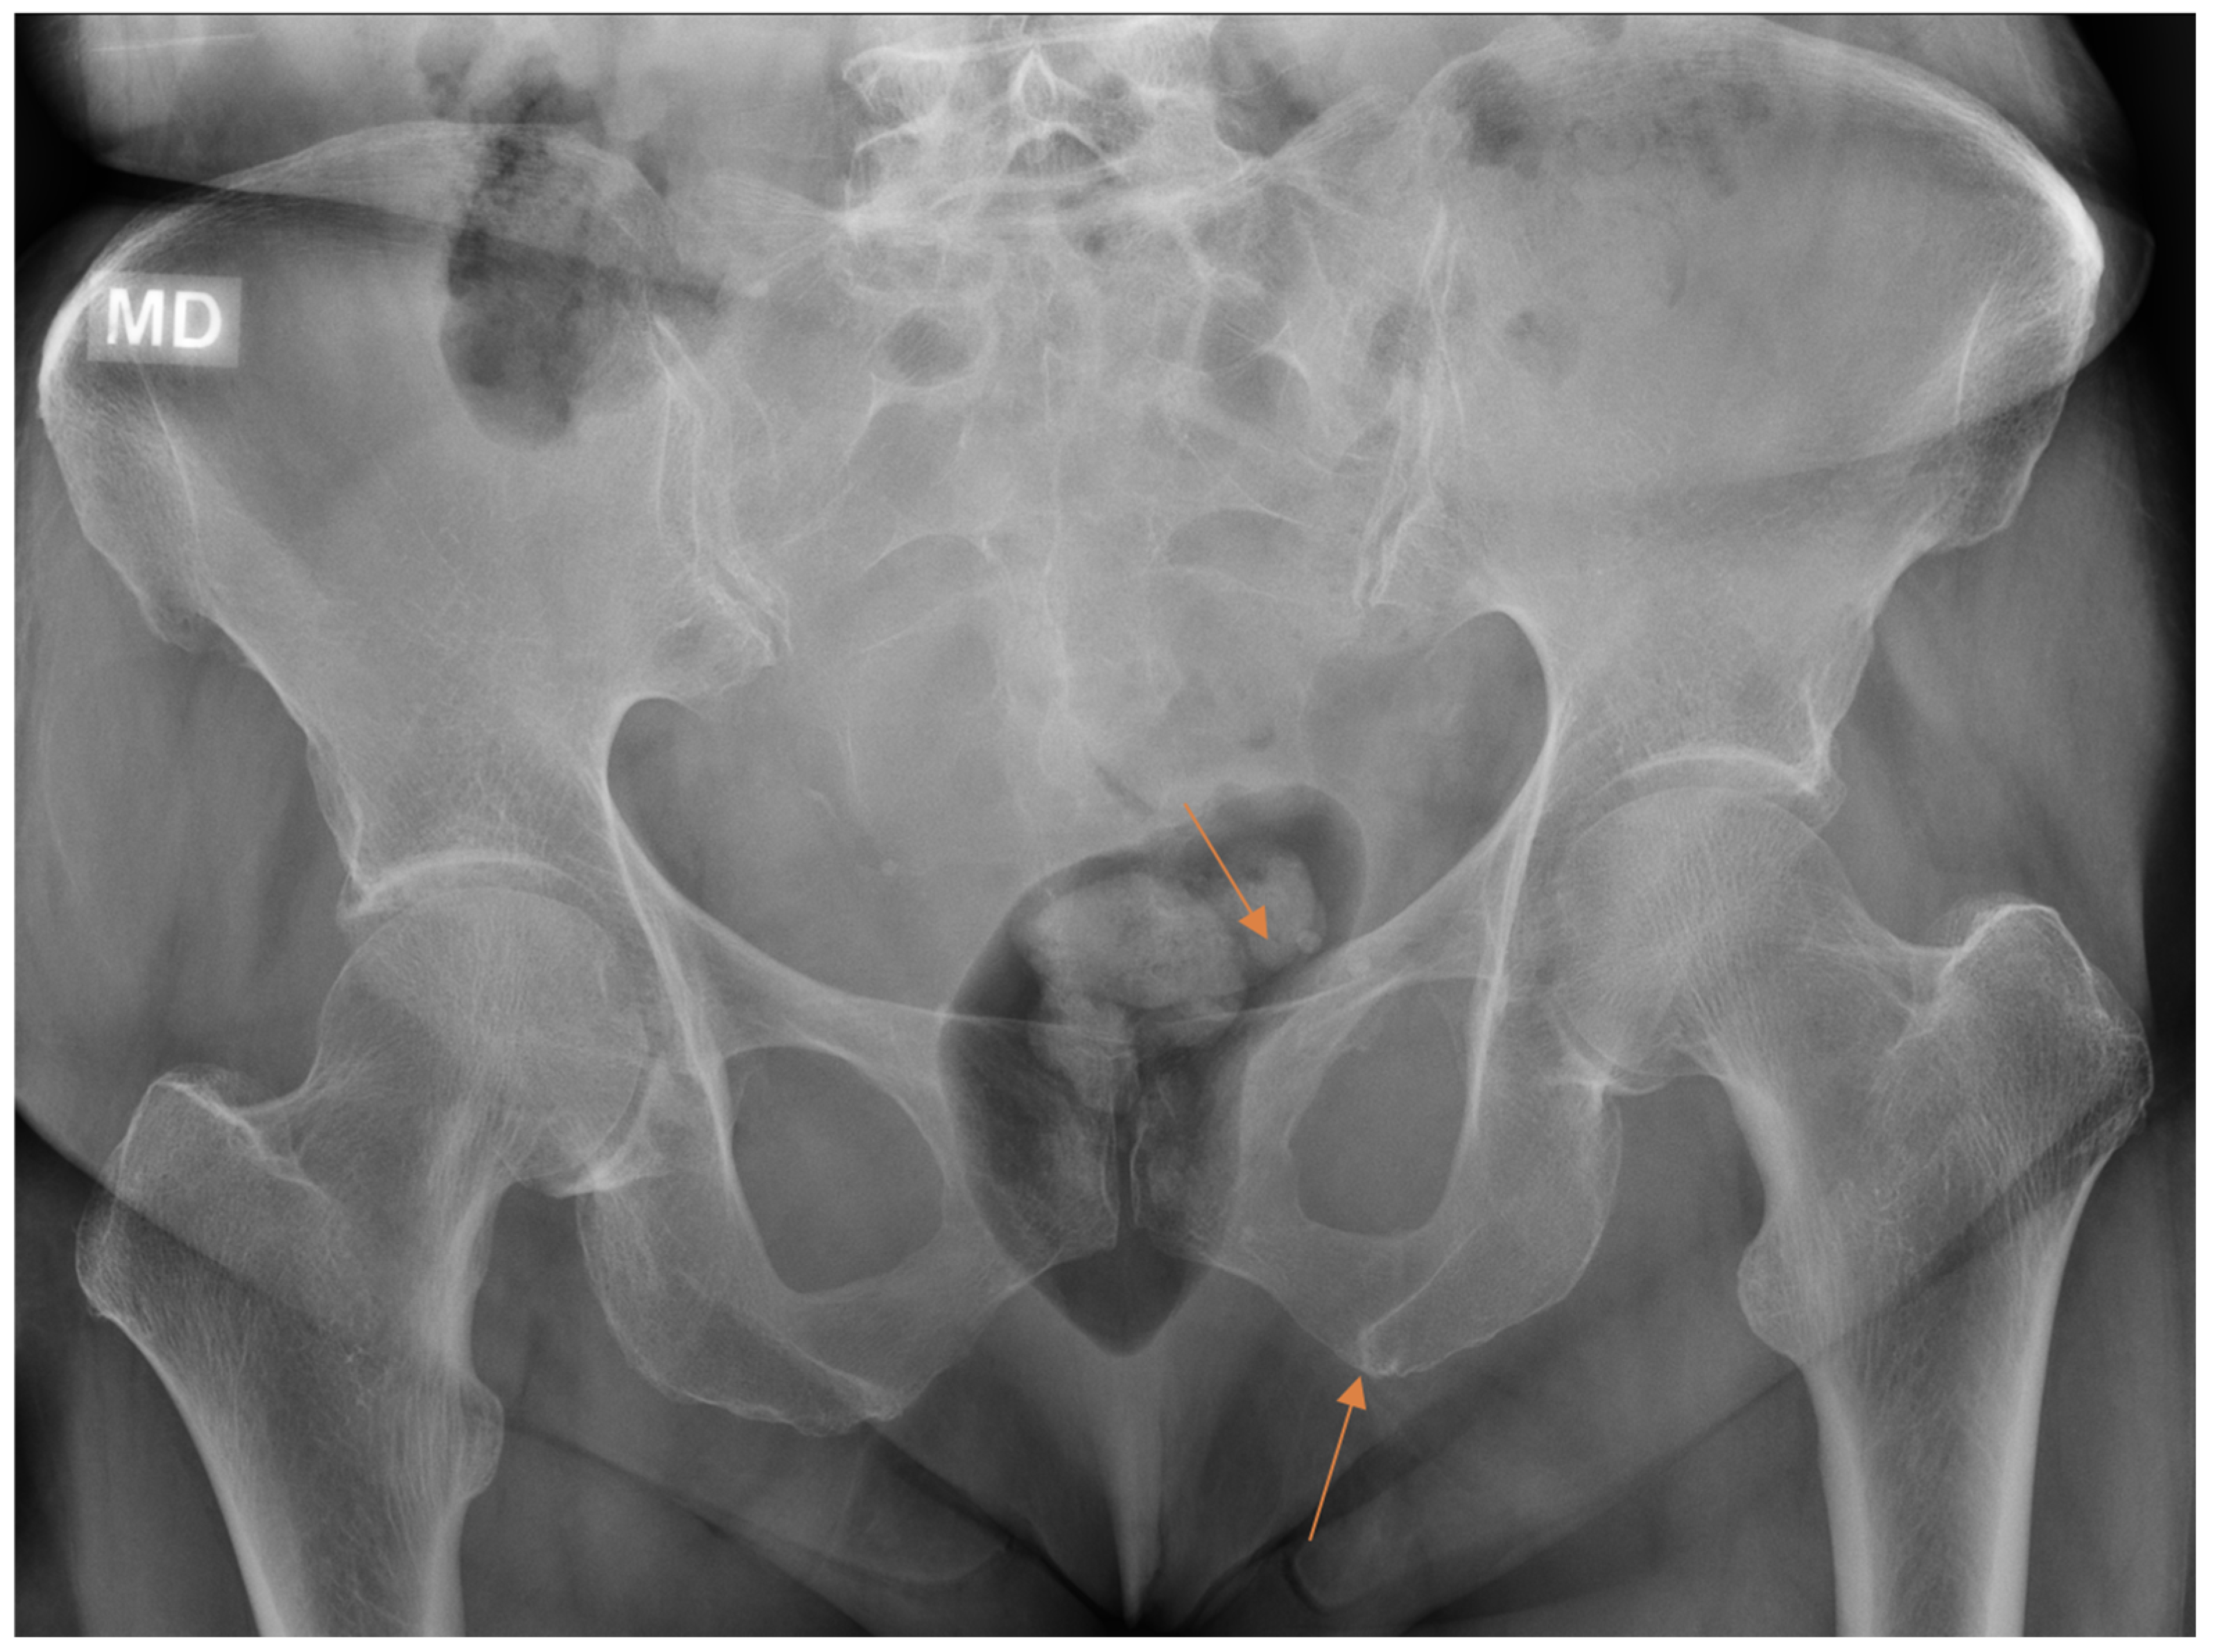

From all the missed findings in the radiographs, 70% (n = 44) were interpreted as having an impact on patient care (p = 0.02), but this did not differ between the radiology specialists and the residents. Findings missed by the radiology specialists (Figure 4 and Figure 5) affected patient care in 71% of cases and overcalls in 31% of cases. Findings missed by the residents (Figure 6) affected patient care in 69% of cases and overcalls in 47% of cases. From all the overcalls in the radiographs, 40% (n = 12) seemed to have an impact on patient care. The most common impact on patient care was a lack of the necessary control study (40%), followed by an unnecessary control study (14%). Interpretation error rarely led to unnecessary operative treatment (1%).

Figure 6.

Patient with pelvic trauma radiographs. Two findings (arrows) initially missed by the resident were later revealed on CT done for other indications.